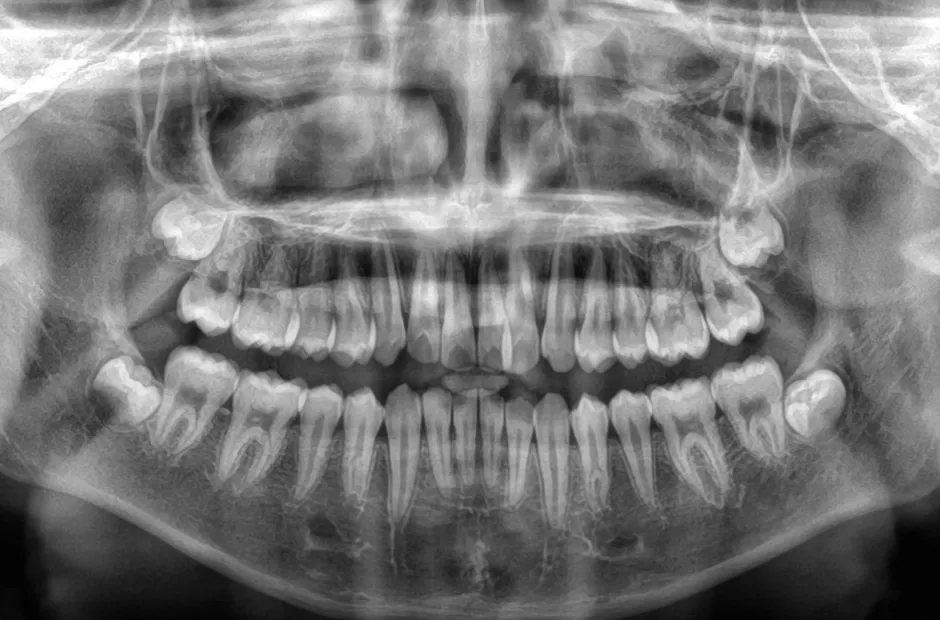

ブラケット矯正

前歯部反対咬合

| 診断名・主訴 | 前歯部反対咬合 |

|---|---|

| 年齢・性別 | 14歳・男性 |

| 治療期間・回数 | 1年2か月 |

| 治療に用いた主な装置 | ブラケット矯正 |

| 抜歯部位 | なし |

| 治療費 | 60万円(税抜) |

| リスク・副作用 | 装置による違和感・疼痛・歯肉退縮・歯根吸収・虫歯のリスクなど |

治療前

治療中

治療後